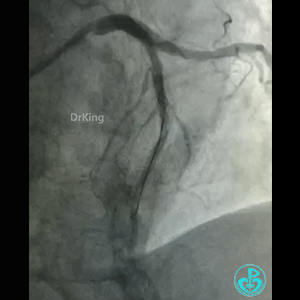

导丝怎么扩真怪!急性心梗前降支导丝通过顺利,球囊扩张后导丝移位很多!不在原来的血管腔!_https://www.jmylbn.com_新闻资讯_第2张

怎么解释导丝和血管的关系?

BMW导丝,预扩前导丝是弯曲的,预扩时球囊也是弯曲的,预扩后导丝拉直,血管的弯曲还在。